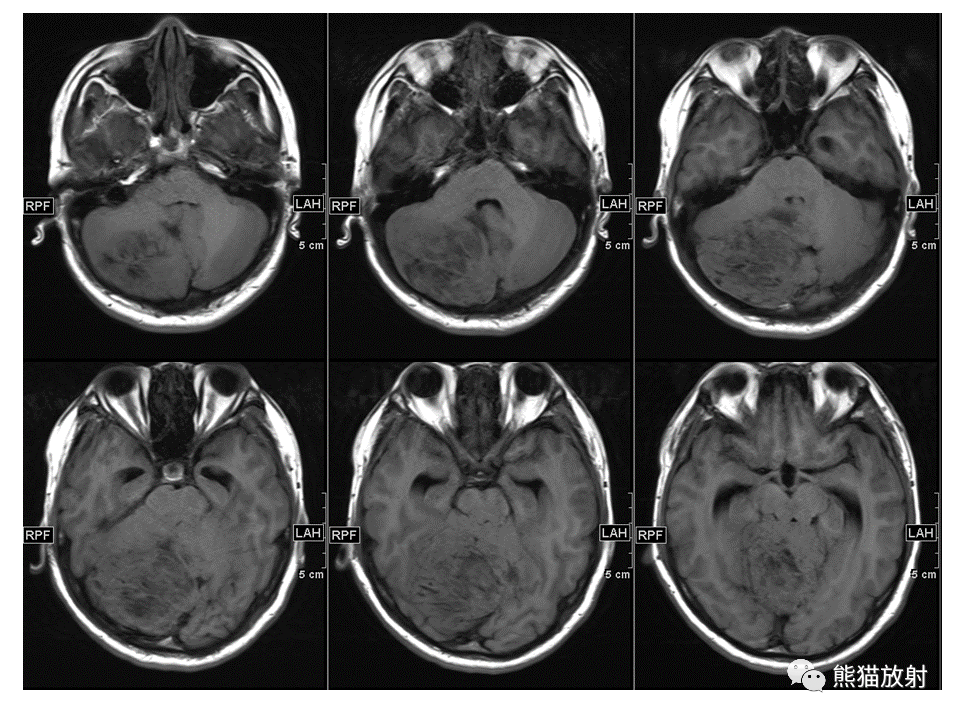

【PPT】小脑发育不良性神经节细胞瘤 VS 成人型髓母细胞瘤-2